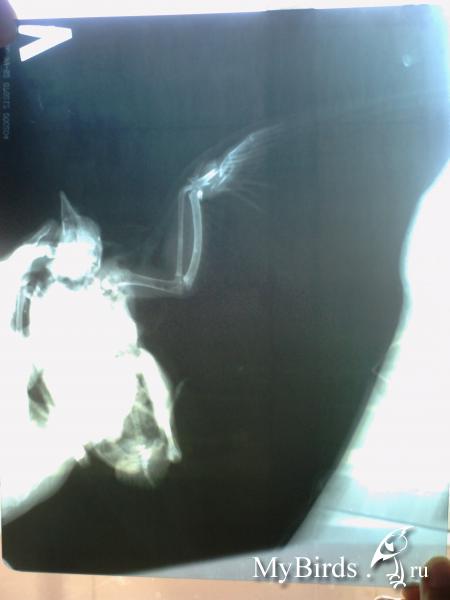

Дела у нас печальные, сделали рентген. Крыло сильно раздроблено - летать больше не сможет к сожалению... Но хуже всего то, что под крылом у него пуля застраля в теле... Вот уже 2 недели у нас живот поправляется, скачет по всему балкону... Возили к ветеринару со снимками, она сказала, что либо пуля сама вылезет, либо всю жизнь с ней проживет. Судя по его состоянию как он ест и крепчает, она его не беспокоит почти, никаких органов не задела. Но Врач не взялась ее вытаскивать, попросила не мучить малыша, а выходить его. Завтра попытаюсь снимки выложить и сфоткать самого голубка. ранка на крыле у него немного кровоточит, когда он бодрячком начинает хлопать крыльями и удирать от нас. Пока мажем иногда йодом и левомеколью.

Судя по снимку пуля свинцовая... какой шанс, что возникнет отравление? Малыш с каждым днем чувствует себя все лучше... так не хочется его мучить.

Выложу снимки, на одном видно пулю, на другом как разломано крыло.